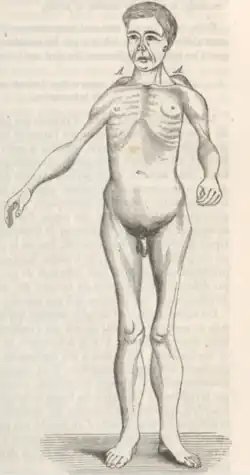

| 1861 | Person with muscular dystrophy depicted by Duchenne. Based on the muscles involved, this person could have had FSHD. |

| 1884 | Landouzy and Dejerine describe a form of childhood progressive muscle atrophy with characteristic involvement of facial muscles distinct from pseudohypertrophic (Duchenne's MD) and spinal muscle atrophy in adults.[128]

Two brothers with FSHD followed by Landouzy and Dejerine Photograph of one brother at age 21. The right scapula is protracted, downwardly rotated, and laterally displaced. Drawing of another brother at age 17. Visible is lumbar hyperlordosis. The upper arm and pectoral muscles appear atrophied. |